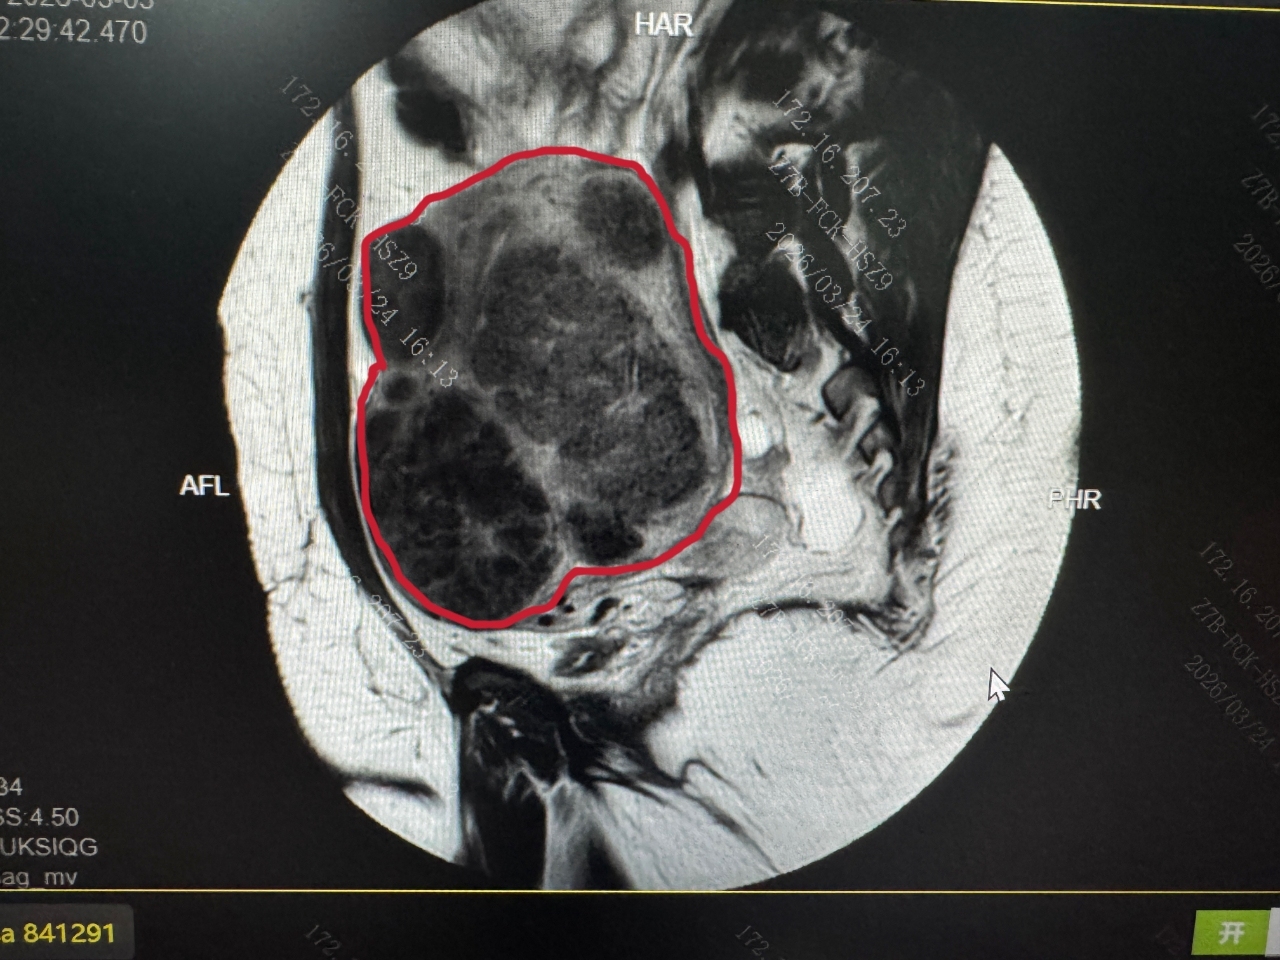

她的子宫被密密麻麻的肌瘤撑大如孕4个月大,面临切除子宫绝境。跨越半个地球来到深圳后,北京大学深圳医院(以下简称“北大深圳医院”)妇产中心团队凭借原创的PUSH 手术(弥漫性子宫病变重建生育力手术), 从她的子宫里地毯式“挖”出 656 颗肌瘤,同时完整保留子宫,重建生育功能,为她未来生娃保住了机会。

安娜的手术,是团队近年来接诊的高难度病例之一,多重风险因素叠加,给手术带来了极大挑战:一是患者体重达216斤,臀围128cm,皮下脂肪厚导致手术术野暴露困难;二是子宫被肌瘤撑至妊娠4个月大小,形态完全失常;三是肌瘤最大直径超10cm,最小的肉眼几乎不可见;四是患者有既往腹腔镜肌瘤剔除术伴大出血病史,盆腔存在广泛致密粘连,解剖结构完全紊乱。

手术过程中,团队先耐心分离盆腔广泛粘连,再从宫底到宫颈、从浆膜层到粘膜层开展“地毯式”排查,对每一颗肌瘤进行精准剥离剔除,同步完成子宫肌层结构的修复重建,全程规避子宫内膜、子宫动脉、输尿管等关键组织器官的损伤风险。最终,经过5小时,团队顺利完成手术,共计剔除可计数肌瘤656颗,装满了整整两个托盘。